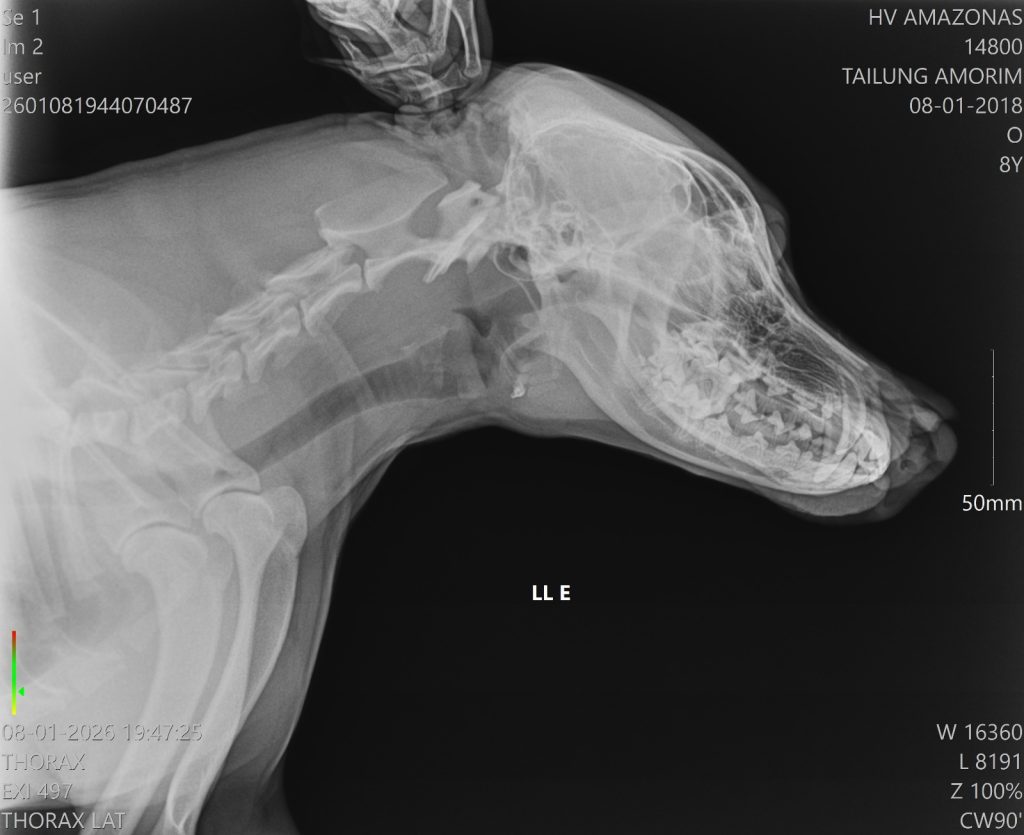

O animal apresentava uma lesão profunda na região do focinho, que foi partido ao meio

A Secretaria de Estado de Proteção Animal (Sepet) socorreu, na noite de quinta-feira (8/01), um cachorro vítima de agressão na comunidade Nossa Senhora do Livramento, localizada no igarapé do Tarumã-Mirim, à margem esquerda do Baixo Rio Negro, zona oeste de Manaus. O animal sofreu um golpe de terçado no focinho e foi encaminhado para atendimento no hospital Público Veterinário do Amazonas (HPVet-AM).

De acordo com a equipe hospitalar, o cachorro apresentava uma lesão profunda na região do focinho, mas estava consciente e respondeu bem ao atendimento. A cirurgia foi bem-sucedida e o animal já foi encaminhado para casa, onde permanecerá em observação pelo tutor, além de seguir acompanhado pela equipe multidisciplinar do HPVet-AM.